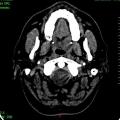

Carcinome épidermoïde du sinus piriforme gauche

CANCER DES VOIES AERODIGESTIVES

CARCINOME EPIDERMOIDE DU SINUS PIRIFORME

Image